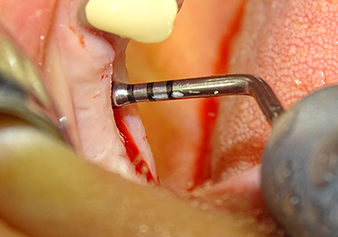

Implant bed preparation and augmentation

Following an intermediate check (Fig. 4) a further preparation step was performed (Fig. 5). Afterwards, the hydraulic Z35P instrument was used to lift the membrane to the desired position (Fig. 6 and 7). This was followed by further piezosurgical preparation of the implant bed, concluded with a rotary bur and shoulder milling cutter up to the implant diameter of 4.8 mm. Before the implant was inserted, the augmentation material (particle size approx. 0.8-1.6 mm) was introduced underneath the Schneiderian membrane (Fig. 8).

The Schneiderian membrane is stretched 1.5-2 mm above the bony access

Fig.4: Intermediate check: The bone height above the maxillary sinus floor is approx. 4 mm palatal and buccal; the Schneiderian membrane is stretched 1.5-2 mm above the bony access.